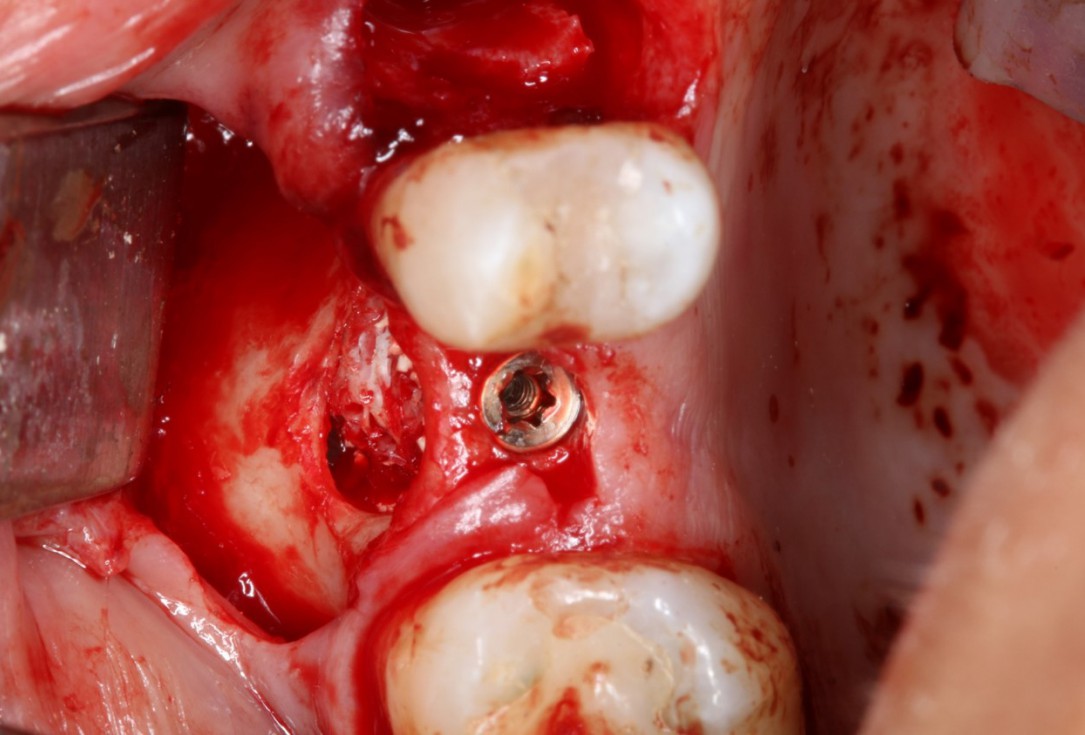

Periimplantitis treatment with maxgraft® bonering - Dr. B. Giesenhagen

Severe periimplantitis at tooth 15 with bone loss up to 1/3 of the implant